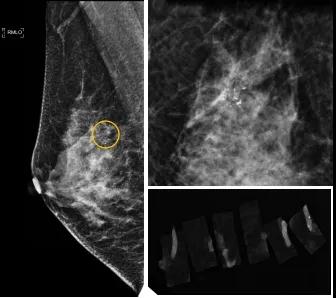

46歲的某女士在西安國(guó)際醫(yī)學(xué)中心醫(yī)院體檢時(shí),行乳腺X線(xiàn)攝影(俗稱(chēng)鉬靶)發(fā)現(xiàn)右乳可疑簇狀鈣化,分布范圍不到1厘米,臨床觸不到,超聲很難發(fā)現(xiàn),但是這種鈣化風(fēng)險(xiǎn)比較高,依據(jù)國(guó)際BI-RADS指南需要明確病理!

西安國(guó)際醫(yī)學(xué)中心醫(yī)院影像診療中心陳寶瑩副主任帶領(lǐng)的團(tuán)隊(duì),采用全數(shù)字化乳腺X線(xiàn)三維立體定位系統(tǒng)可實(shí)施。這個(gè)團(tuán)隊(duì)的成員大部分來(lái)自知名三甲醫(yī)院,有著十余年影像引導(dǎo)下乳腺介入診療的經(jīng)驗(yàn),X線(xiàn)引導(dǎo)穿刺定位和活檢例數(shù)居西北前列。為減少患者創(chuàng)傷,在詳細(xì)判讀了患者資料,并與患者及甲乳外科劉曉敏主任充分溝通的基礎(chǔ)上,團(tuán)隊(duì)確定采用全數(shù)字化乳腺X線(xiàn)三維立體定位系統(tǒng)下實(shí)施粗針活檢。

當(dāng)天,乳腺X線(xiàn)三維立體定位系統(tǒng)清晰顯示出了所有鈣化。為了獲取充足的組織量,保證病理診斷的準(zhǔn)確性,團(tuán)隊(duì)選用14G穿刺針并多點(diǎn)、多角度取材,組織取出后,又立即在高清標(biāo)本攝影系統(tǒng)中進(jìn)行投照,從而確定了取出組織中具有足夠的可疑鈣化。整個(gè)過(guò)程患者無(wú)任何不適,活檢結(jié)束后即回家觀察。